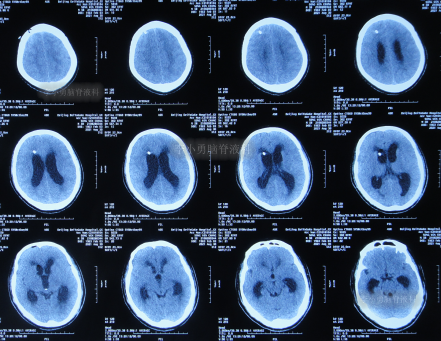

2021年8月28日(颈椎病术后3个月零21天并发颅内感染、脑积水),入院时:体温高,意识模糊,精神差,小便失禁,不能遵命活动,颈后有手术疤痕(图-3);入院时头颅CT示脑积水(图-4)。

图-4:入院时头颅CT

2021年9月4日(入院第7天),头颅CT示脑室明显缩小(图-9)。

图-9:2021年9月4日头颅CT